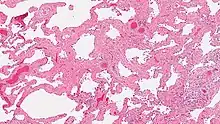

Smoking-related interstitial fibrosis (SRIF) is an abnormality in the lungs characterized by excessive collagen deposition within the walls of the air sacs (interstitial fibrosis). This abnormality can be seen with a microscope and diagnosed by pathologists. It is caused by cigarette smoking.[1][2]

The defining feature of smoking-related interstitial fibrosis is a distinctive/unique type of fibrosis characterized by "ropey" collagen bundles within the walls of the air sacs (alveoli), almost always in association with other smoking-related abnormalities such as pigmented macrophages and emphysema.[6]